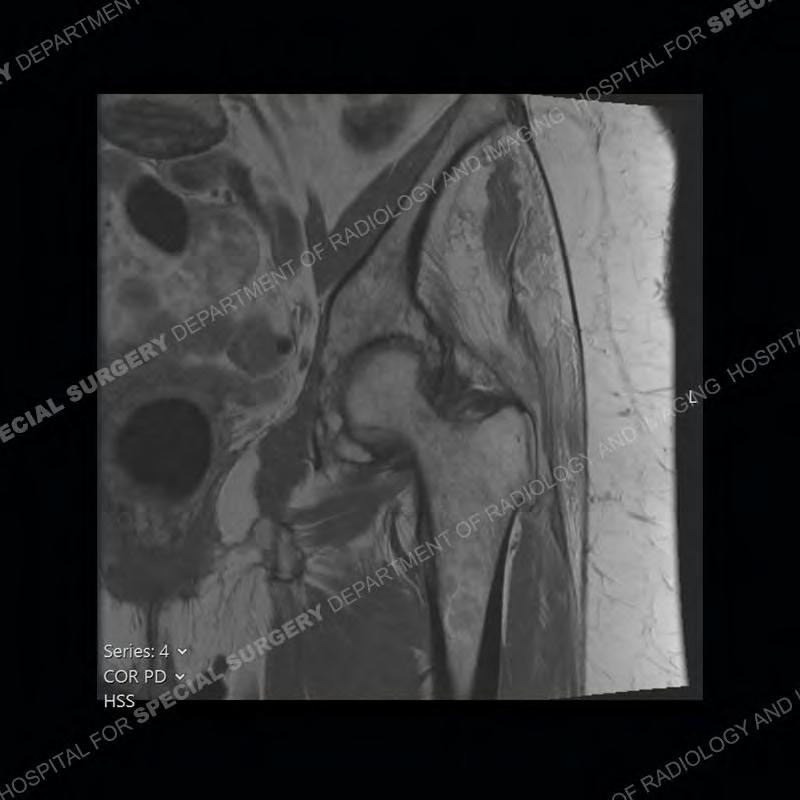

The radiograph is not particularly contributory in this case. The MRI demonstrates markedly abnormal architecture of the gluteus minimus and anterolateral band of the gluteus medius. Portions of the tendons are high signal, portions are highly attenuated, and portions are disrupted. A large, complex fluid collection is present in the adjacent soft tissue.

Diagnosis: Gluteal Tendinosis and Disruption with Complex Trochanteric Bursal Collection

Not as much of a diagnostic dilemma as many of the other cases shown but just a nice example of the pathology seen of the gluteal tendons and a cause of trochanteric pain. Although, frequently thought of in isolation, trochanteric bursitis or bursal thickening is much more commonly a reactive change to underlying pathology of the subjacent gluteal tendons. The gluteus medius is divided into a posterior band and an anterolateral band. Tendinosis and partial tearing very commonly will involve the gluteus minimus and especially the more posterior fibers and then propagate into the anterior lateral band of the gluteus medius. Involvement of the posterior band of the medius is much less common and engenders a marked degree of functional impairment.

The bursae about the greater trochanter can be a little bit confusing especially given the terminology. Trochanteric bursitis is implied to mean the subgluteus maximus bursa which is present deep to the maximus and just lateral/superficial to the trochanter. That is the bursa involved in this case. In this case the complexity of the bursa relates to the tendon tearing with inflammatory change and probably hemorrhage accounting for the complexity. Two other, less frequently involved bursa are also present. The subgluteus medius and subgluteus minimus bursa are found just deep to the named tendons. Although pathology does frequently follow the previously described pattern it is possible to have isolated pathology to either the medius or minimus.